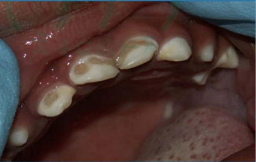

孩子最常見的蛀牙——奶瓶齲

每個人都會蛀牙,特別是孩子。今天介紹的是孩子最常見的一種蛀牙——奶瓶齲。

就像這個孩子10個月大時,剛萌出不久的上排前牙就開始齲壞,外層白色的牙釉質(zhì)一點點脫落,但父母卻未注意,到20個月大時,牙齒已經(jīng)齲壞嚴重,只剩下牙根了。